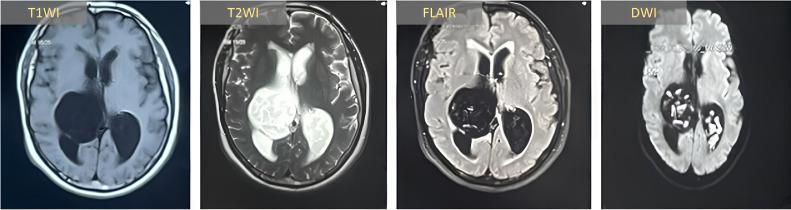

Epidermoid cysts of the lateral ventricle are rare, benign intracranial lesions originating from ectopic embryonic epithelial cells, comprising only 0.2% of intracranial neoplasms. Although often asymptomatic initially, they may eventually cause mass effects or cerebrospinal fluid (CSF) obstruction as they enlarge. Accurate diagnosis-typically achieved via diffusion-weighted imaging (DWI)-is essential, as these cysts can mimic other intraventricular pathologies. Surgical resection remains the definitive treatment, though their deep-seated location and proximity to critical neurovascular structures pose significant challenges. This series describes 3 cases of lateral ventricle epidermoid cysts in patients presenting with progressive symptoms, including headaches, visual deficits, and neurological impairments, consistent with elevated intracranial pressure. Preoperative imaging, notably DWI, confirmed the diagnoses by demonstrating characteristic restricted diffusion. Near-total resection was achieved using microsurgical and endoscopic techniques, preserving vital structures and resulting in favorable postoperative outcomes with symptom resolution. However, 1 patient experienced persistent visual deficits due to delayed intervention. Advanced imaging, particularly DWI, is indispensable for precise diagnosis, while combined microscopic-endoscopic approaches optimize resection and reduce neurological risks. Early diagnosis and tailored surgical strategies are crucial for optimal outcomes. This series underscores the need for standardized management guidelines and identifies barriers to long-term follow-up, such as financial constraints.

摘要